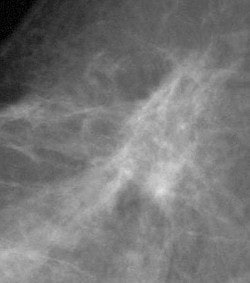

DSPM images acquired on the Mammomat 3000 Nova, including zoom (middle) and spot magnification (below). Images courtesy of Dr. Wolfgang Matzek.

![]() |